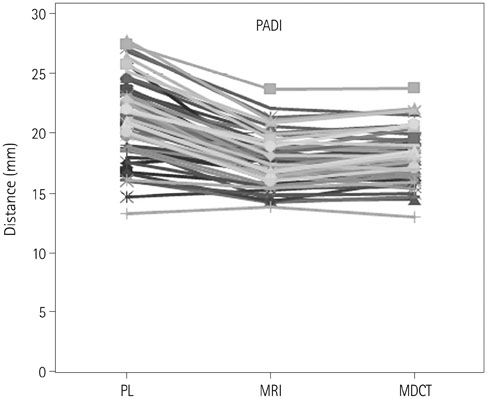

To determine the normal values of the anterior atlantodental interval (AADI) and posterior atlantodental interval (PADI) on plain radiography, multidetector CT (MDCT) and MRI, as well as the dural sac width and spinal cord diameter at the atlantoaxial joint level on MRI.

In total, 60 subjects underwent plain radiography, MRI and MDCT. We obtained values for AADI and PADI on plain radiography, MDCT, and MRI, and for dural sac width and spinal cord diameter on MRI. Two radiologists independently measured each value and a consensus was reached.

The average AADI was 1.5 +/- 0.5 mm on plain radiography, 1.4 +/- 0.3 mm on MDCT, and 1.6 +/- 0.5 mm on MRI. The average PADI was 20.6 +/- 2.4 mm on plain radiography, 18.0 +/- 2.1 mm on MDCT, and 17.7 +/- 1.9 mm on MRI. The dural sac width was 13.7 +/- 1.8 mm, and the spinal cord diameter was 7.8 +/- 0.7 mm. Interobserver agreement was 0.701-0.927 and intraobserver agreement was 0.681-0.937.

AADI values obtained on MDCT are significantly lower than those obtained on plain radiography or MRI. PADI values obtained on plain radiography are significantly higher than those obtained on MDCT or MRI. The dural sac width is most closely correlated with PADI values on MDCT. PADI seems to be easier to measure, more relevant, and clinically useful than AADI.